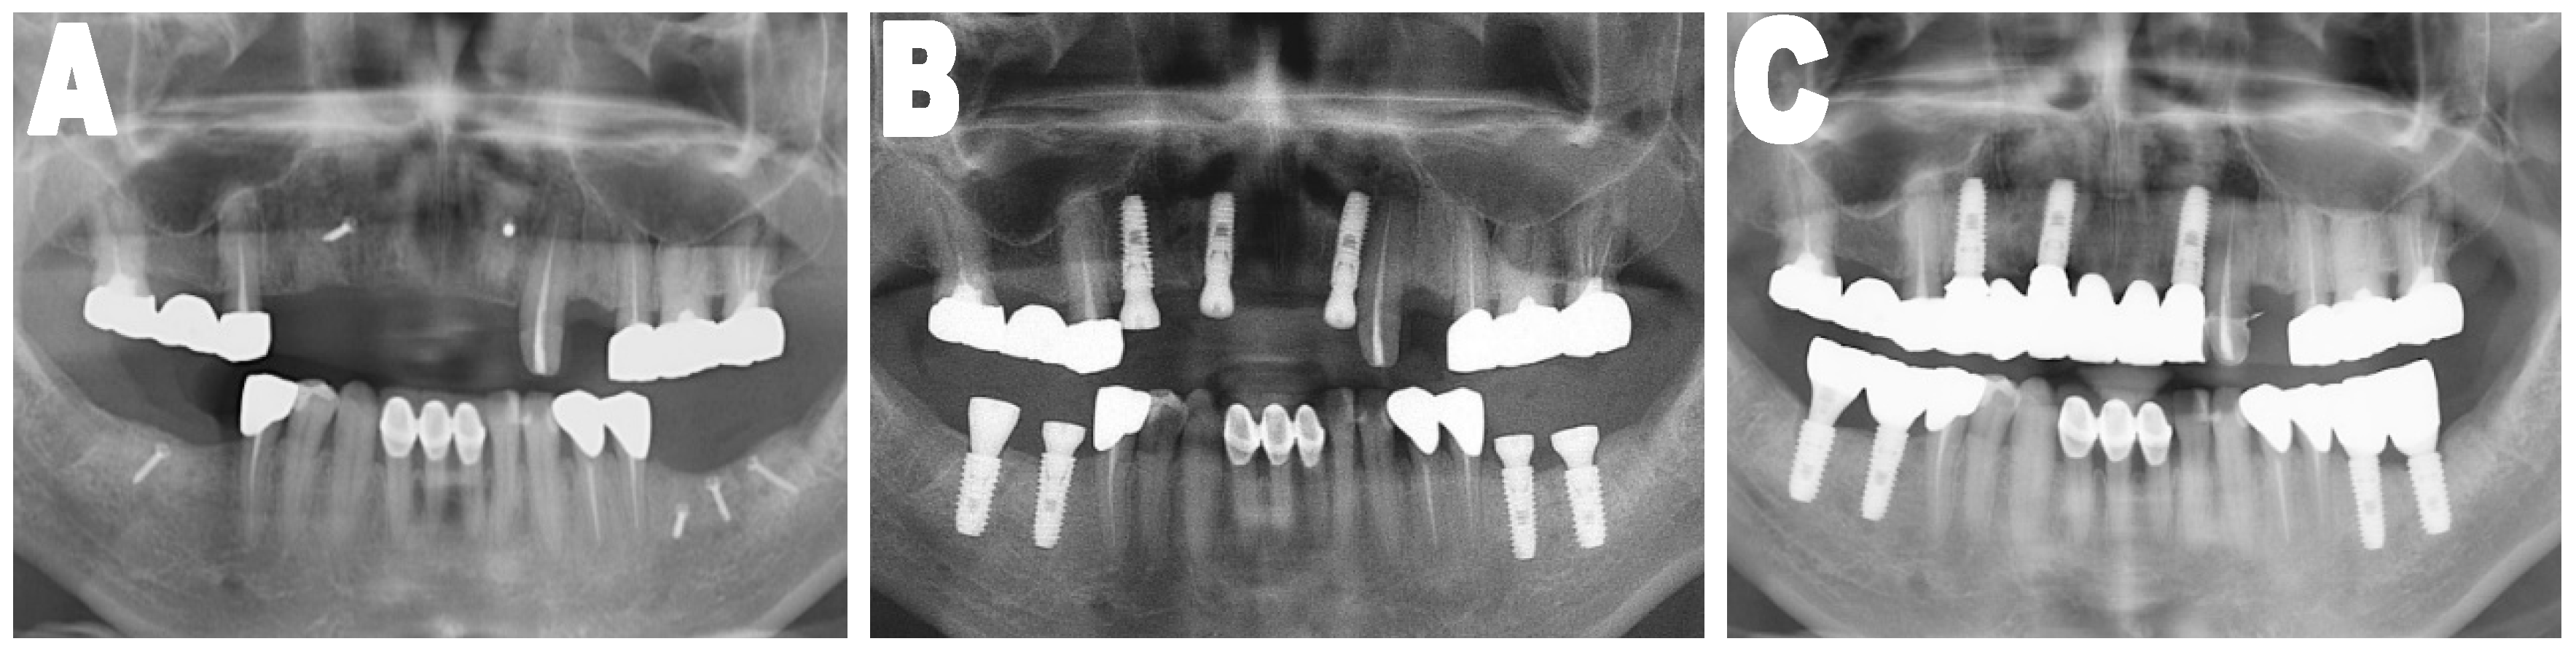

OPTGs taken immediately, four months, and at the one year following implant placement were used to evaluate the stability of the grafted bone which was covered with CBM and the success of the installed implants, see Figure 2. The number of exposed threads of the implants was measured and evaluated. This was considered as an indication of the postoperative maintenance of the bone grafts and the success of implants. The subject of the measurement was always the implant in which the greatest number of exposed threads was present for each patient. Other variables were recorded, such as the type of membrane, sex, age, site of implant placement (maxilla/mandible, anterior/posterior, horizontally/vertically grafted, external/internal implants type, and one- or two-step installation of the implant fixtures.

Figure 2.

Orthopantomographic images. (A) On the day of the mandibular block bone graft; (B) Immediately after installation of implants; (C) One year after installation of the implants. Analysis between (B,C) orthopantomographic X-ray (OPTG) images were performed to check the number of exposed threads.